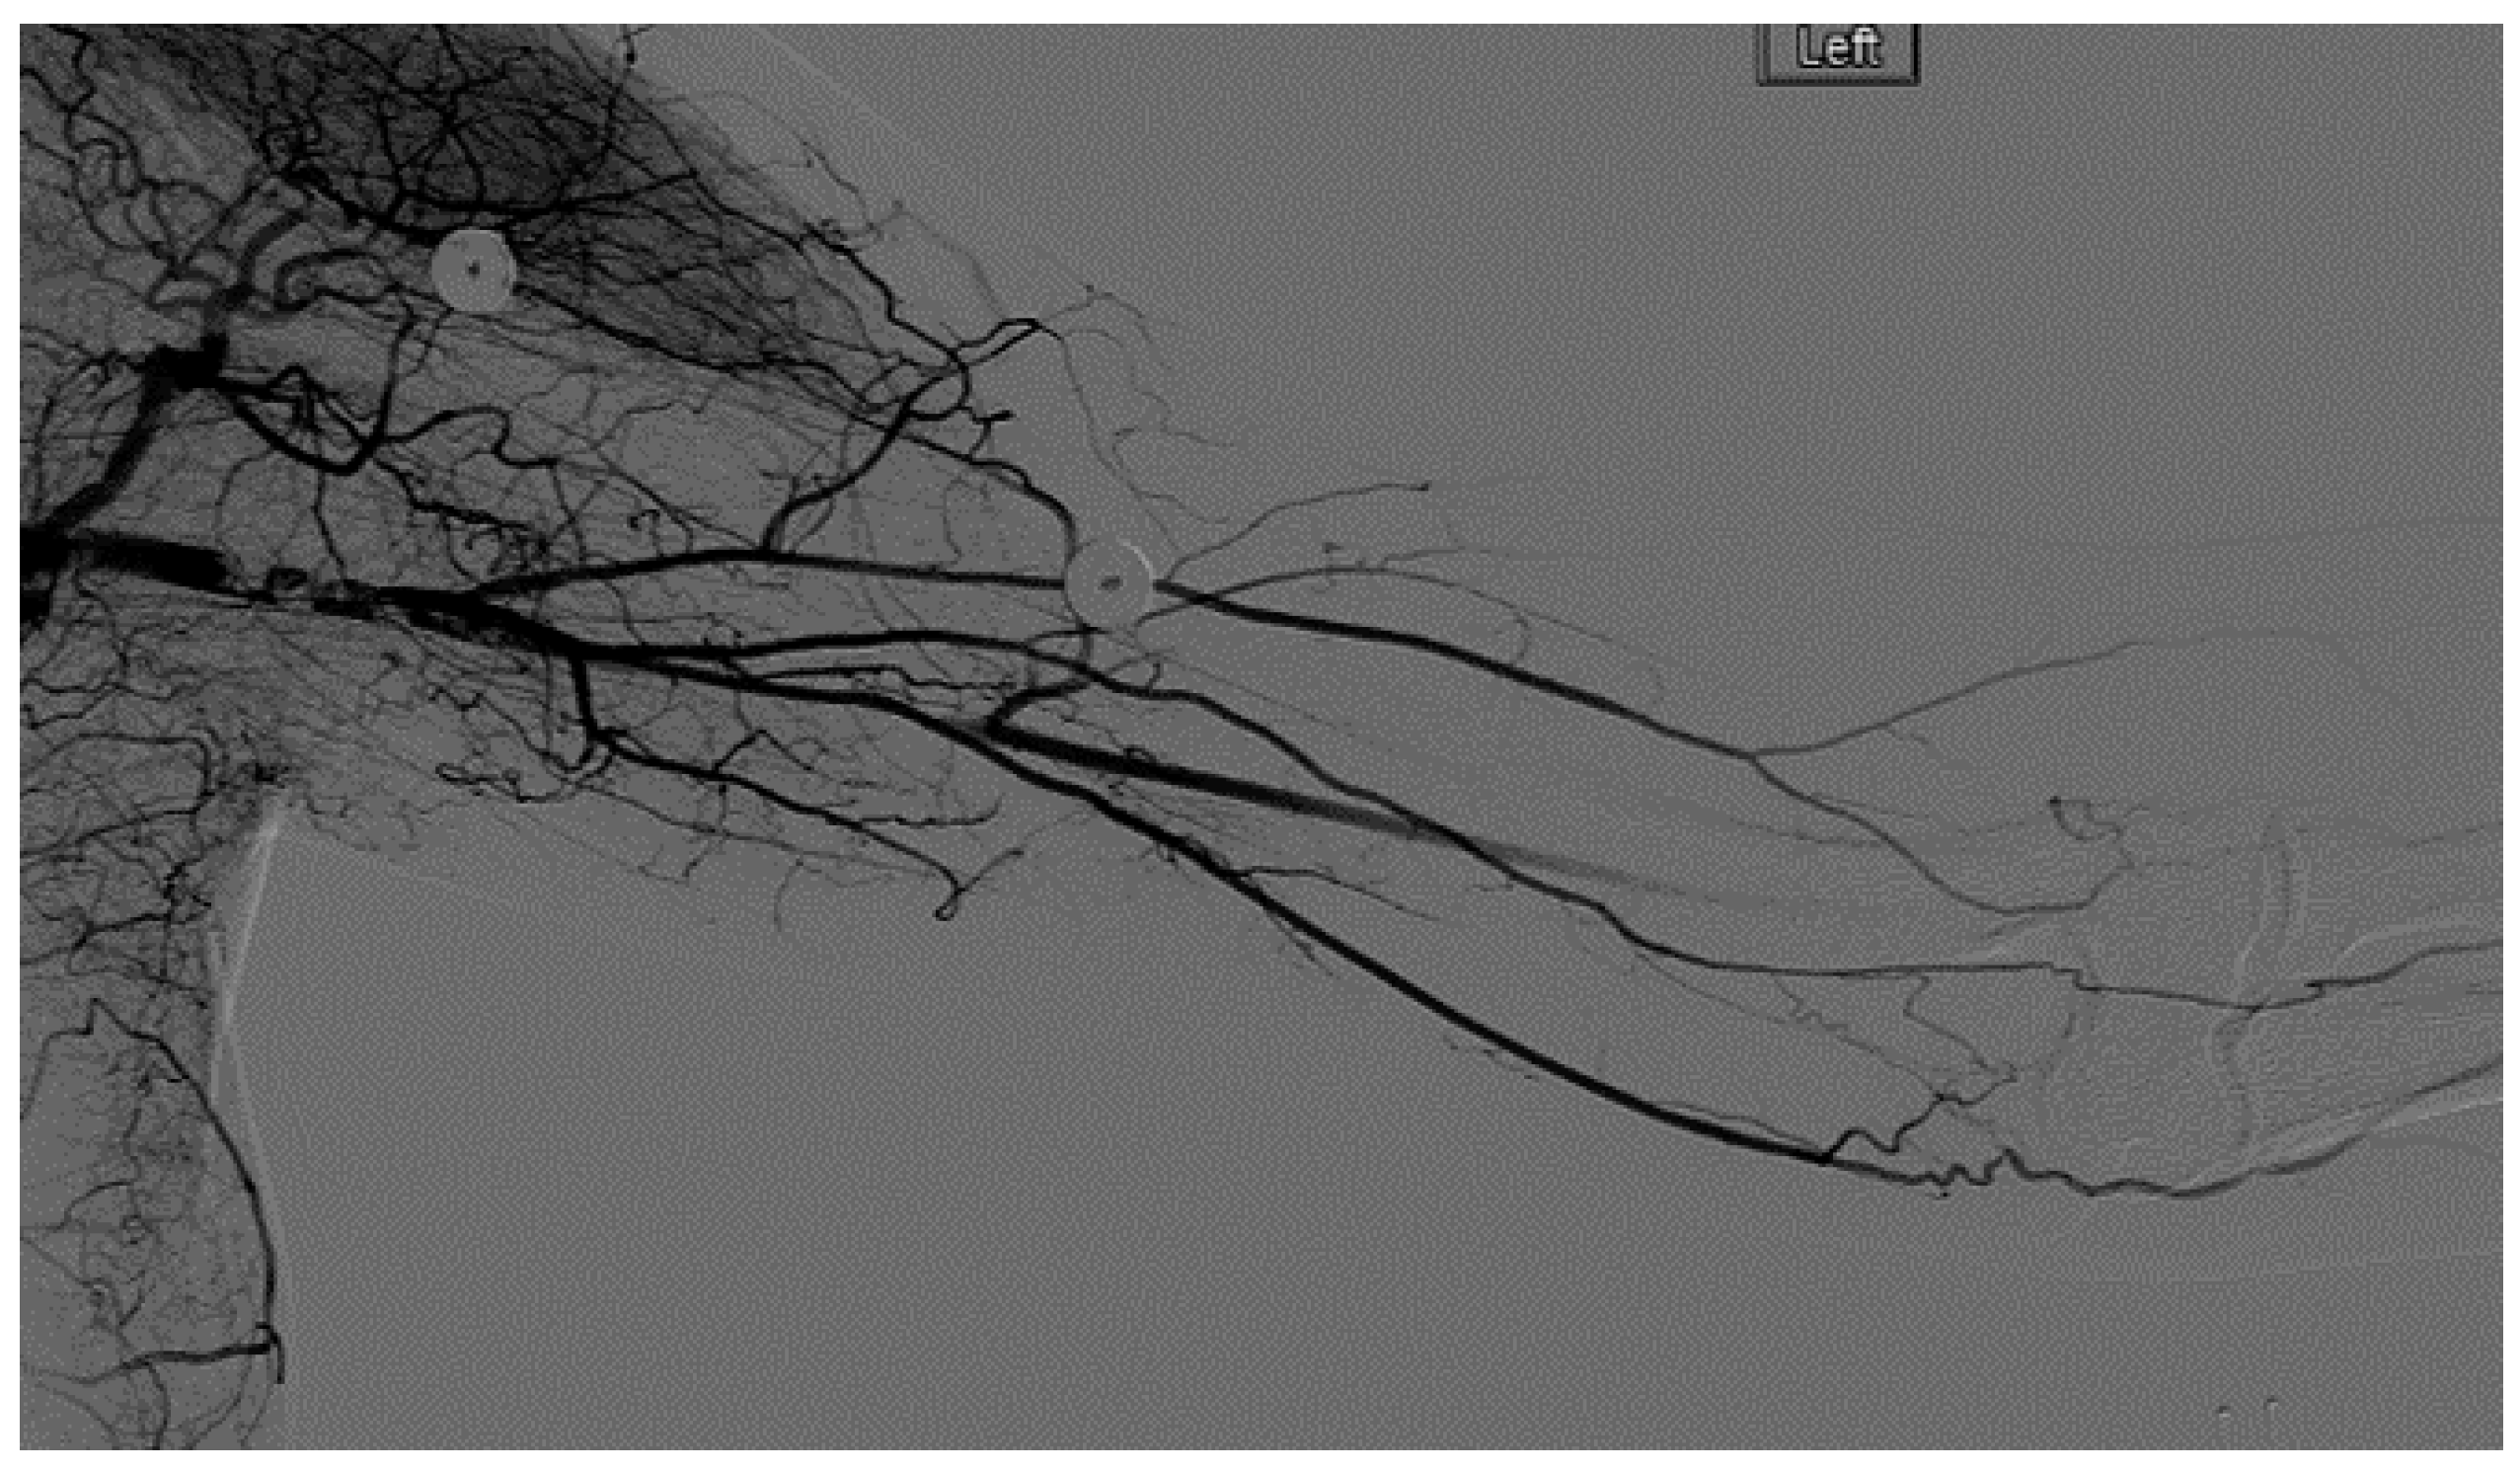

A heparin drip was then initiated, and she was taken to the catheterization lab for thrombolysis. This was carried out with Alteplase for 48 h as the patient had strong collaterals and was not in limb-threat (Figure 7, Figure 8, Figure 9, Figure 10 and Figure 11). However, her radial artery remained occluded. She was then taken to the operating room for thromboembolectomy of the left brachial and radial arteries (Figure 12). She was continued on anticoagulation post-operatively and was discharged.

Figure 7.

Left subclavian arteriography demonstrating a thrombosed brachial artery at the mid-humeral level and extensive collateralization proximally.

Figure 8.

Left subclavian arteriography in an ATOS patient in stress position demonstrating a totally occluded subclavian artery.